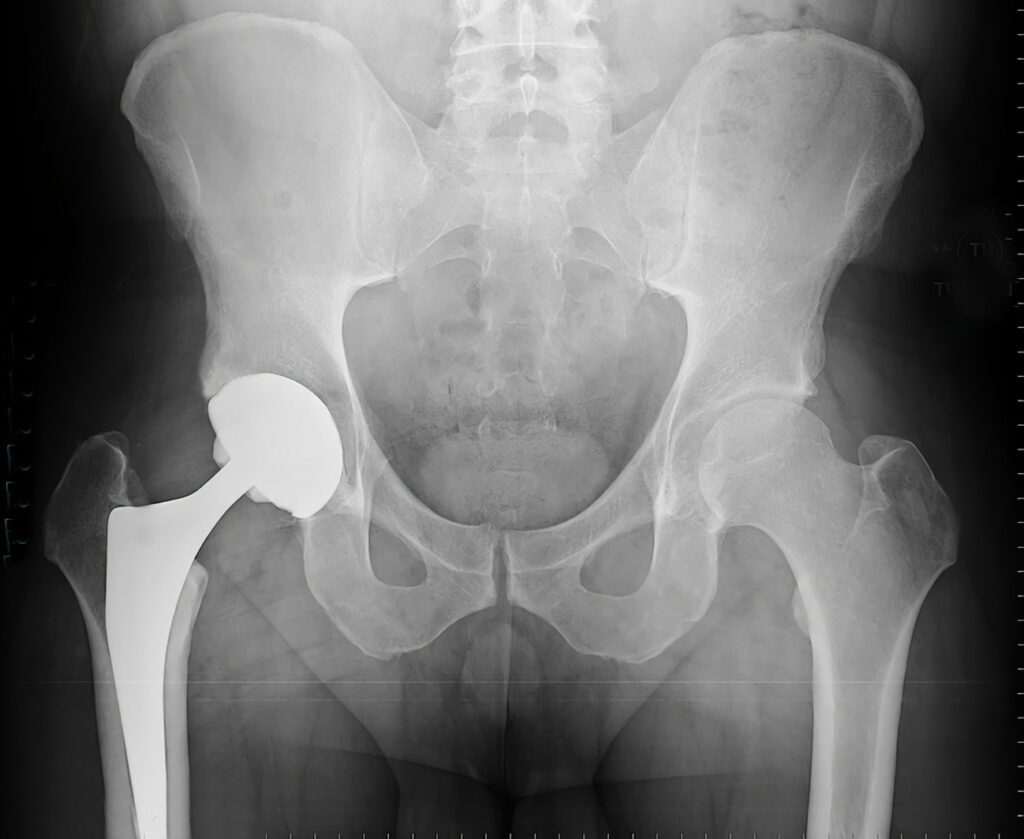

A depender da resposta terapêutica, podemos lançar mão de infiltrações articulares, cirurgias preservadoras e até cirurgias para substituir a articulação por uma prótese.